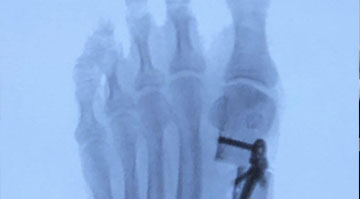

Minimally Invasive Surgery: On the day of the procedure, our skilled surgeons use specialized instruments and techniques to correct the bunion with minimal tissue disruption. The surgery is typically performed on an outpatient basis, allowing you to return home the same day.